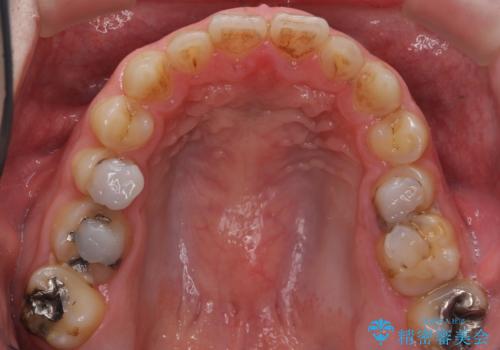

綺麗な仕上がりにご満足下さいました。

奥歯の咬み合わせも良くなったと喜んで頂けました。

患者様の理想とする韓流アイドルの写真を技工士さんに送り、最終的なクラウンの形や色をできるだけ理想に近づけられるよう努めました。

下顎はホワイトニングを行っております。

「今後も繰り返しホワイトニングをして白さを追求していきます!」とおっしゃって下さいました。

クラウンの種類:オールセラミッククラウン スタンダード